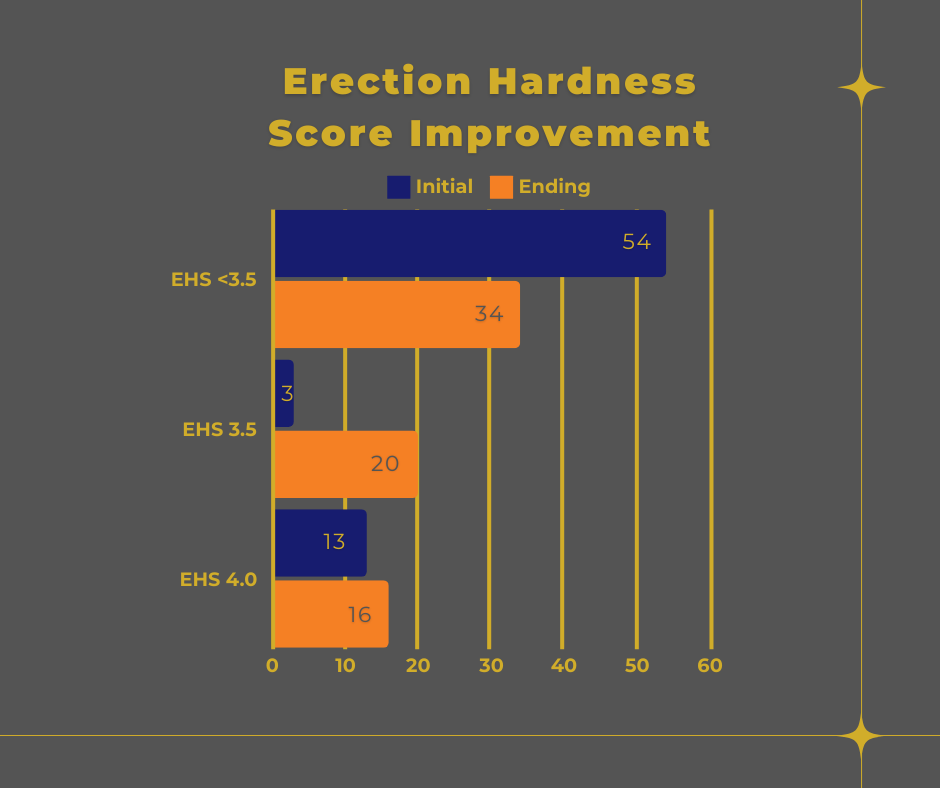

Figure 4 EHS Patient Improvement

This study was a Peyronie's disease/plaque study and shows reduction in volume of plaque however, the results may be easier to see when reviewing the changes recognized in the degree of curve. Of the total 70 patients reviewed, 16 were initially found to show an erection grade of 3.5 or higher. The data reviewed is the measured erections grade found on the first and last vascular study to allow for comparison. Initially, of the total 70 patients, 13 patients were evaluated at an erection grade of 4, after treatments there was a total of 16 patients. Initially only 3 pts were graded at a 3.5 but there was a total of 20 patients on the re-evaluation. It could be that those 3 patients who were graded at a 3.5 moved up to a 4 and the 20 came from patients who initially were found with erections grades at a 3 or lower. Therefore, to begin with only 16 patients had erection grades of 3.5 or 4 out of the original 70 participants but afterward 36 patients showed a grade of 3.5 or 4.

Figure 4 EHS Patient Improvement